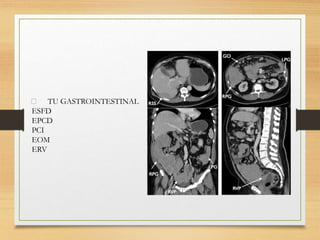

TU GASTROINTESTINAL

ESFD

EPCD

PCI

EOM

ERV